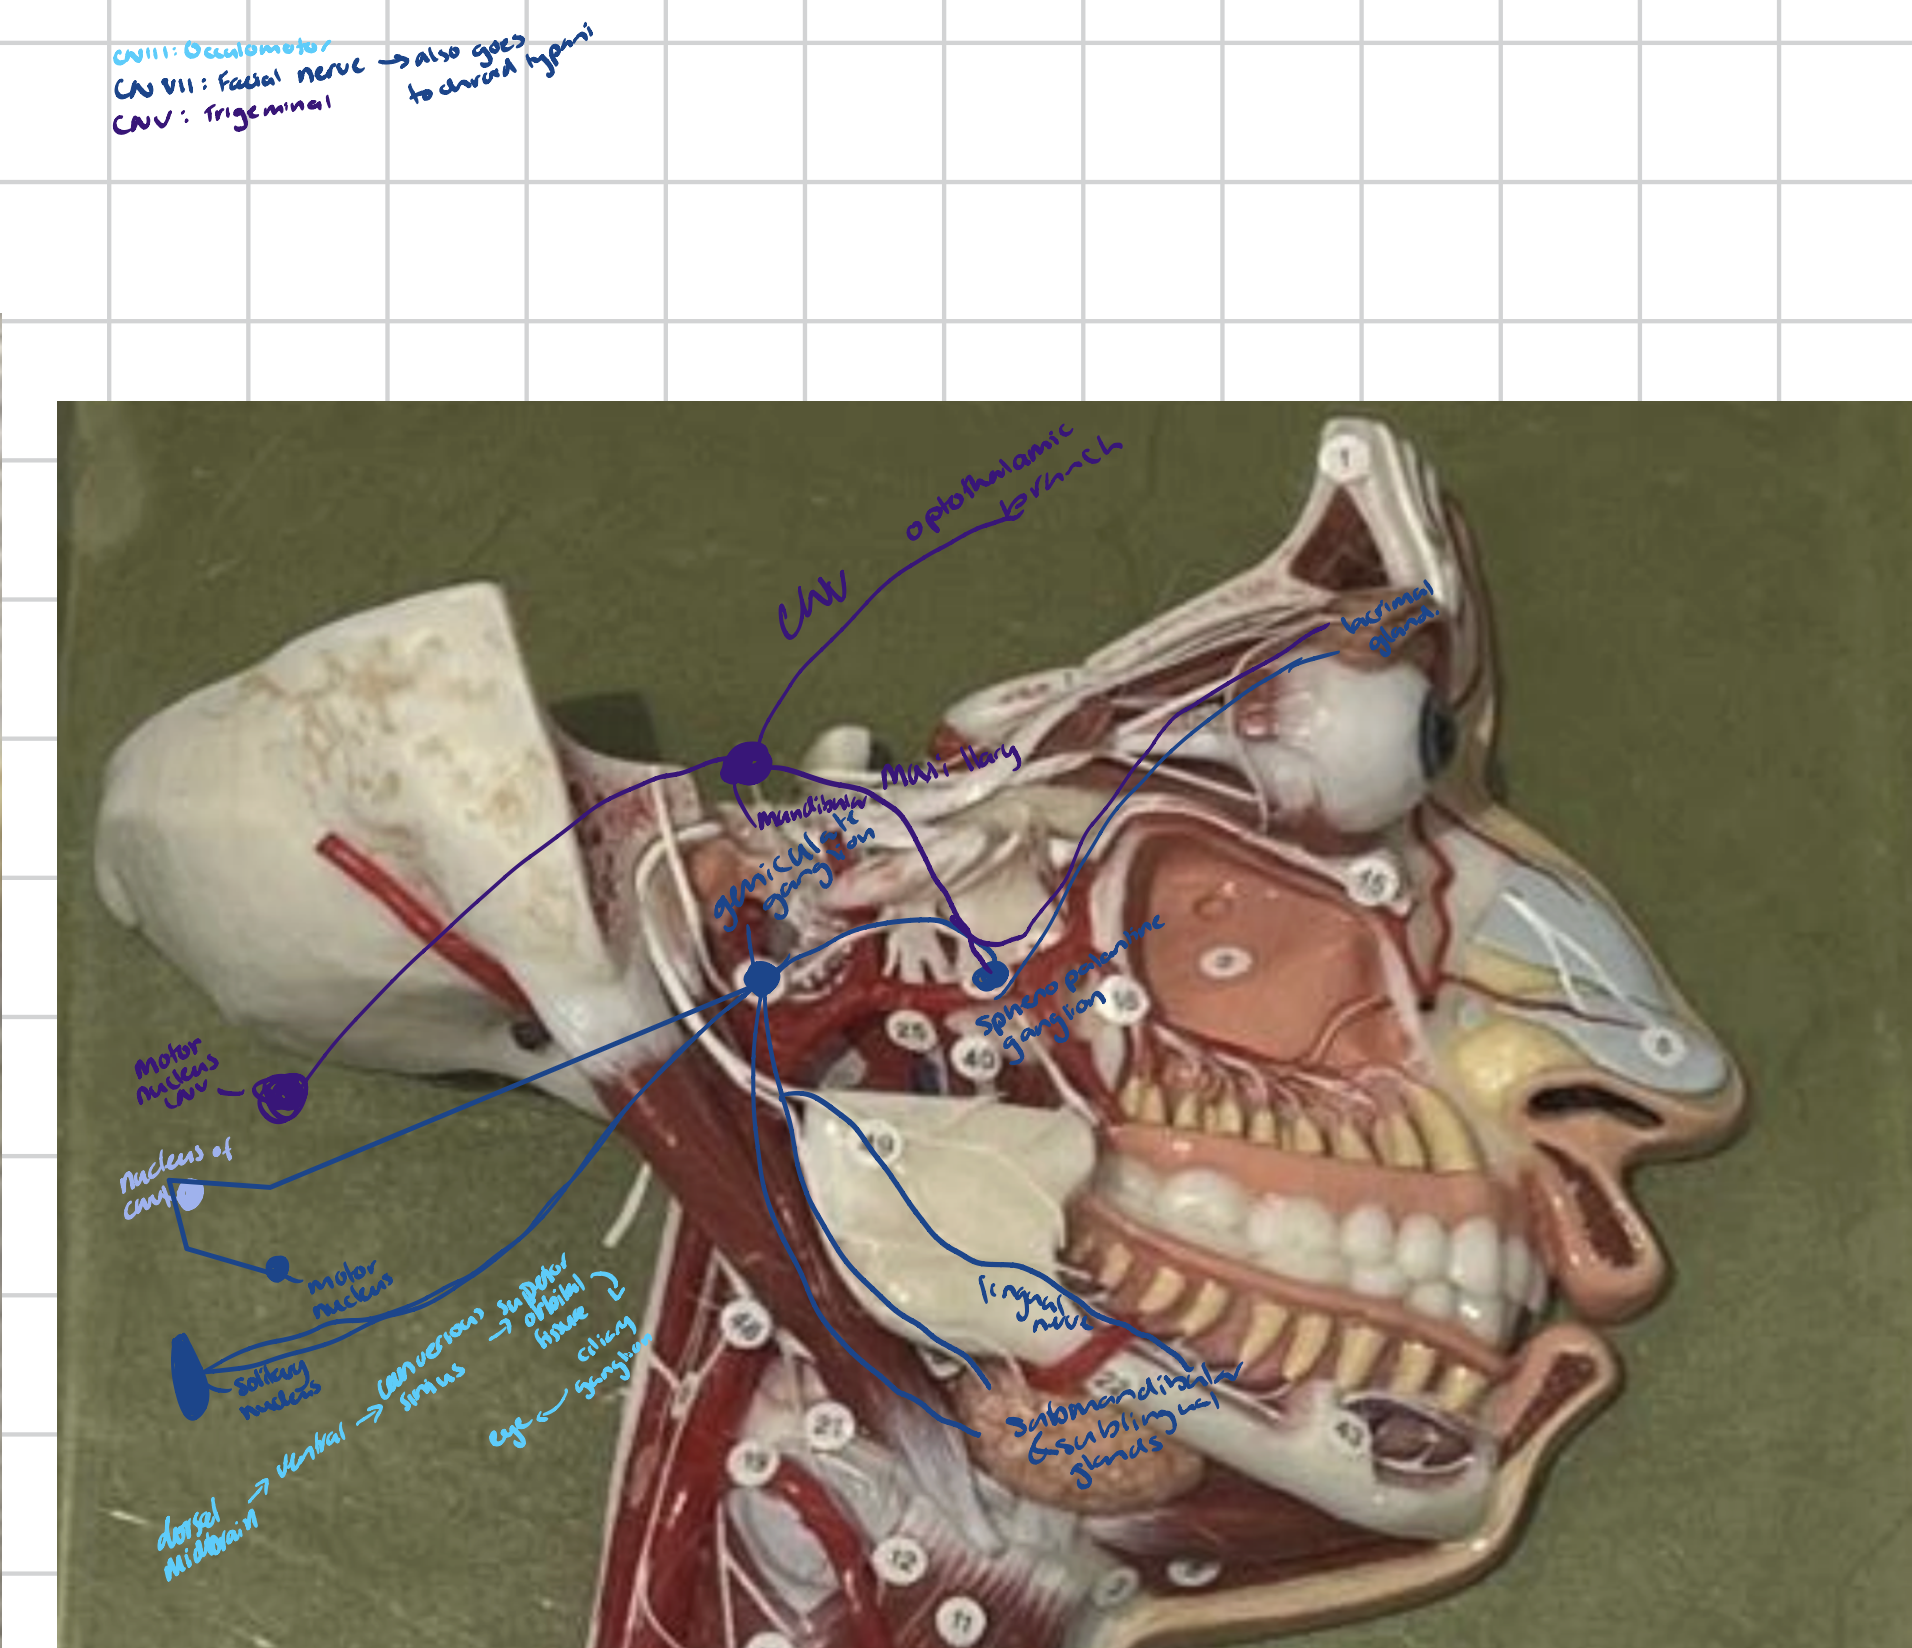

Trigeminal/Gasserian ganglion

A large, crescent-shaped sensory ganglion of the fifth cranial nerve (CN V) that is located in the middle cranial fossa.

Contains cell bodies for the three main branches of the trigeminal nerve.

Cranial Nerves